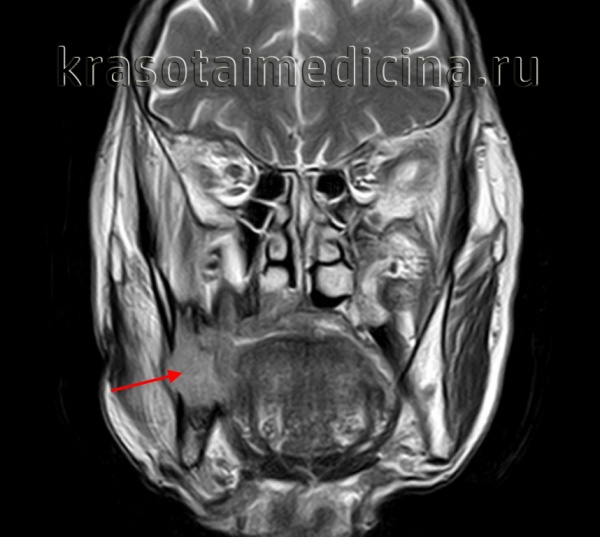

Амелобластома – наиболее частая одонтогенная опухоль челюстей, склонная к инвазивному, местно-деструирующему росту. Поражает преимущественно нижнюю челюсть в области ее тела, угла или ветви. Развивается внутрикостно, может прорастать в мягкие ткани дна полости рта и десны. Чаще проявляется в возрасте 20-40 лет.

В начальном периоде амелобластома протекает бессимптомно, однако по мере увеличения размеров опухоли возникает деформация челюсти, асимметрия лица. Зубы в области поражения часто становятся подвижными и смещаются, может отмечаться зубная боль. Опухоль верхней челюсти может прорастать в полость носа, гайморову пазуху, орбиту; деформировать твердое нёбо и альвеолярный отросток. Нередки случаи нагноения, рецидивирования и малигнизации амелобластомы. Клиническое течение таких опухолей челюсти, как амелобластическая фиброма и одонтоамелобластома, напоминает амелобластому.